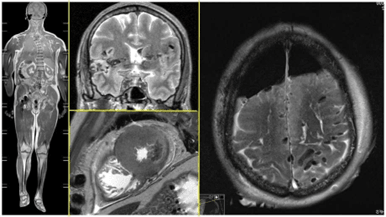

Inselspital Bern has pioneered the use of 7-Tesla Magnetic Resonance Imaging (7T-MRI), a cutting-edge tool enhancing diagnostic capabilities in neurology. Dr. Piotr Radojewski from the University Institute for Diagnostic and Interventional Neuroradiology elaborates on its transformative potential in an interview. The ultrahigh-field 7T-MRI provides unparalleled imaging resolution, unveiling subtle brain structures and processes previously undetectable. Its applications are extensive, from detecting minor anomalies to evaluating complex conditions like epilepsy, multiple sclerosis (MS), and cerebrovascular diseases. For instance, 7T-MRI allowed the accurate diagnosis of a cortical dysplasia in an epilepsy patient, paving the way for targeted surgical intervention. Such advancements exemplify its superiority in identifying lesions invisible to standard 3T-MRI. In MS research, 7T-MRI has revealed cortical lesions and paramagnetic rim lesions, offering critical insights into disease progression and therapy optimization. Additionally, it is pivotal in diagnosing challenging conditions like CNS vasculitis and evaluating the safety of novel Alzheimer’s medications by identifying amyloid-related imaging abnormalities. Despite its promise, 7T-MRI is not yet a routine tool, given limited availability and ongoing evidence accumulation. Dr. Radojewski envisions its integration into standard clinical practice, akin to the historical trajectory of 3T-MRI, emphasizing the importance of collaborative feedback loops between clinicians, researchers, and technologists. This innovation underscores Inselspital’s commitment to leveraging technology for enhanced patient outcomes and sets a benchmark for the future of neuroimaging.